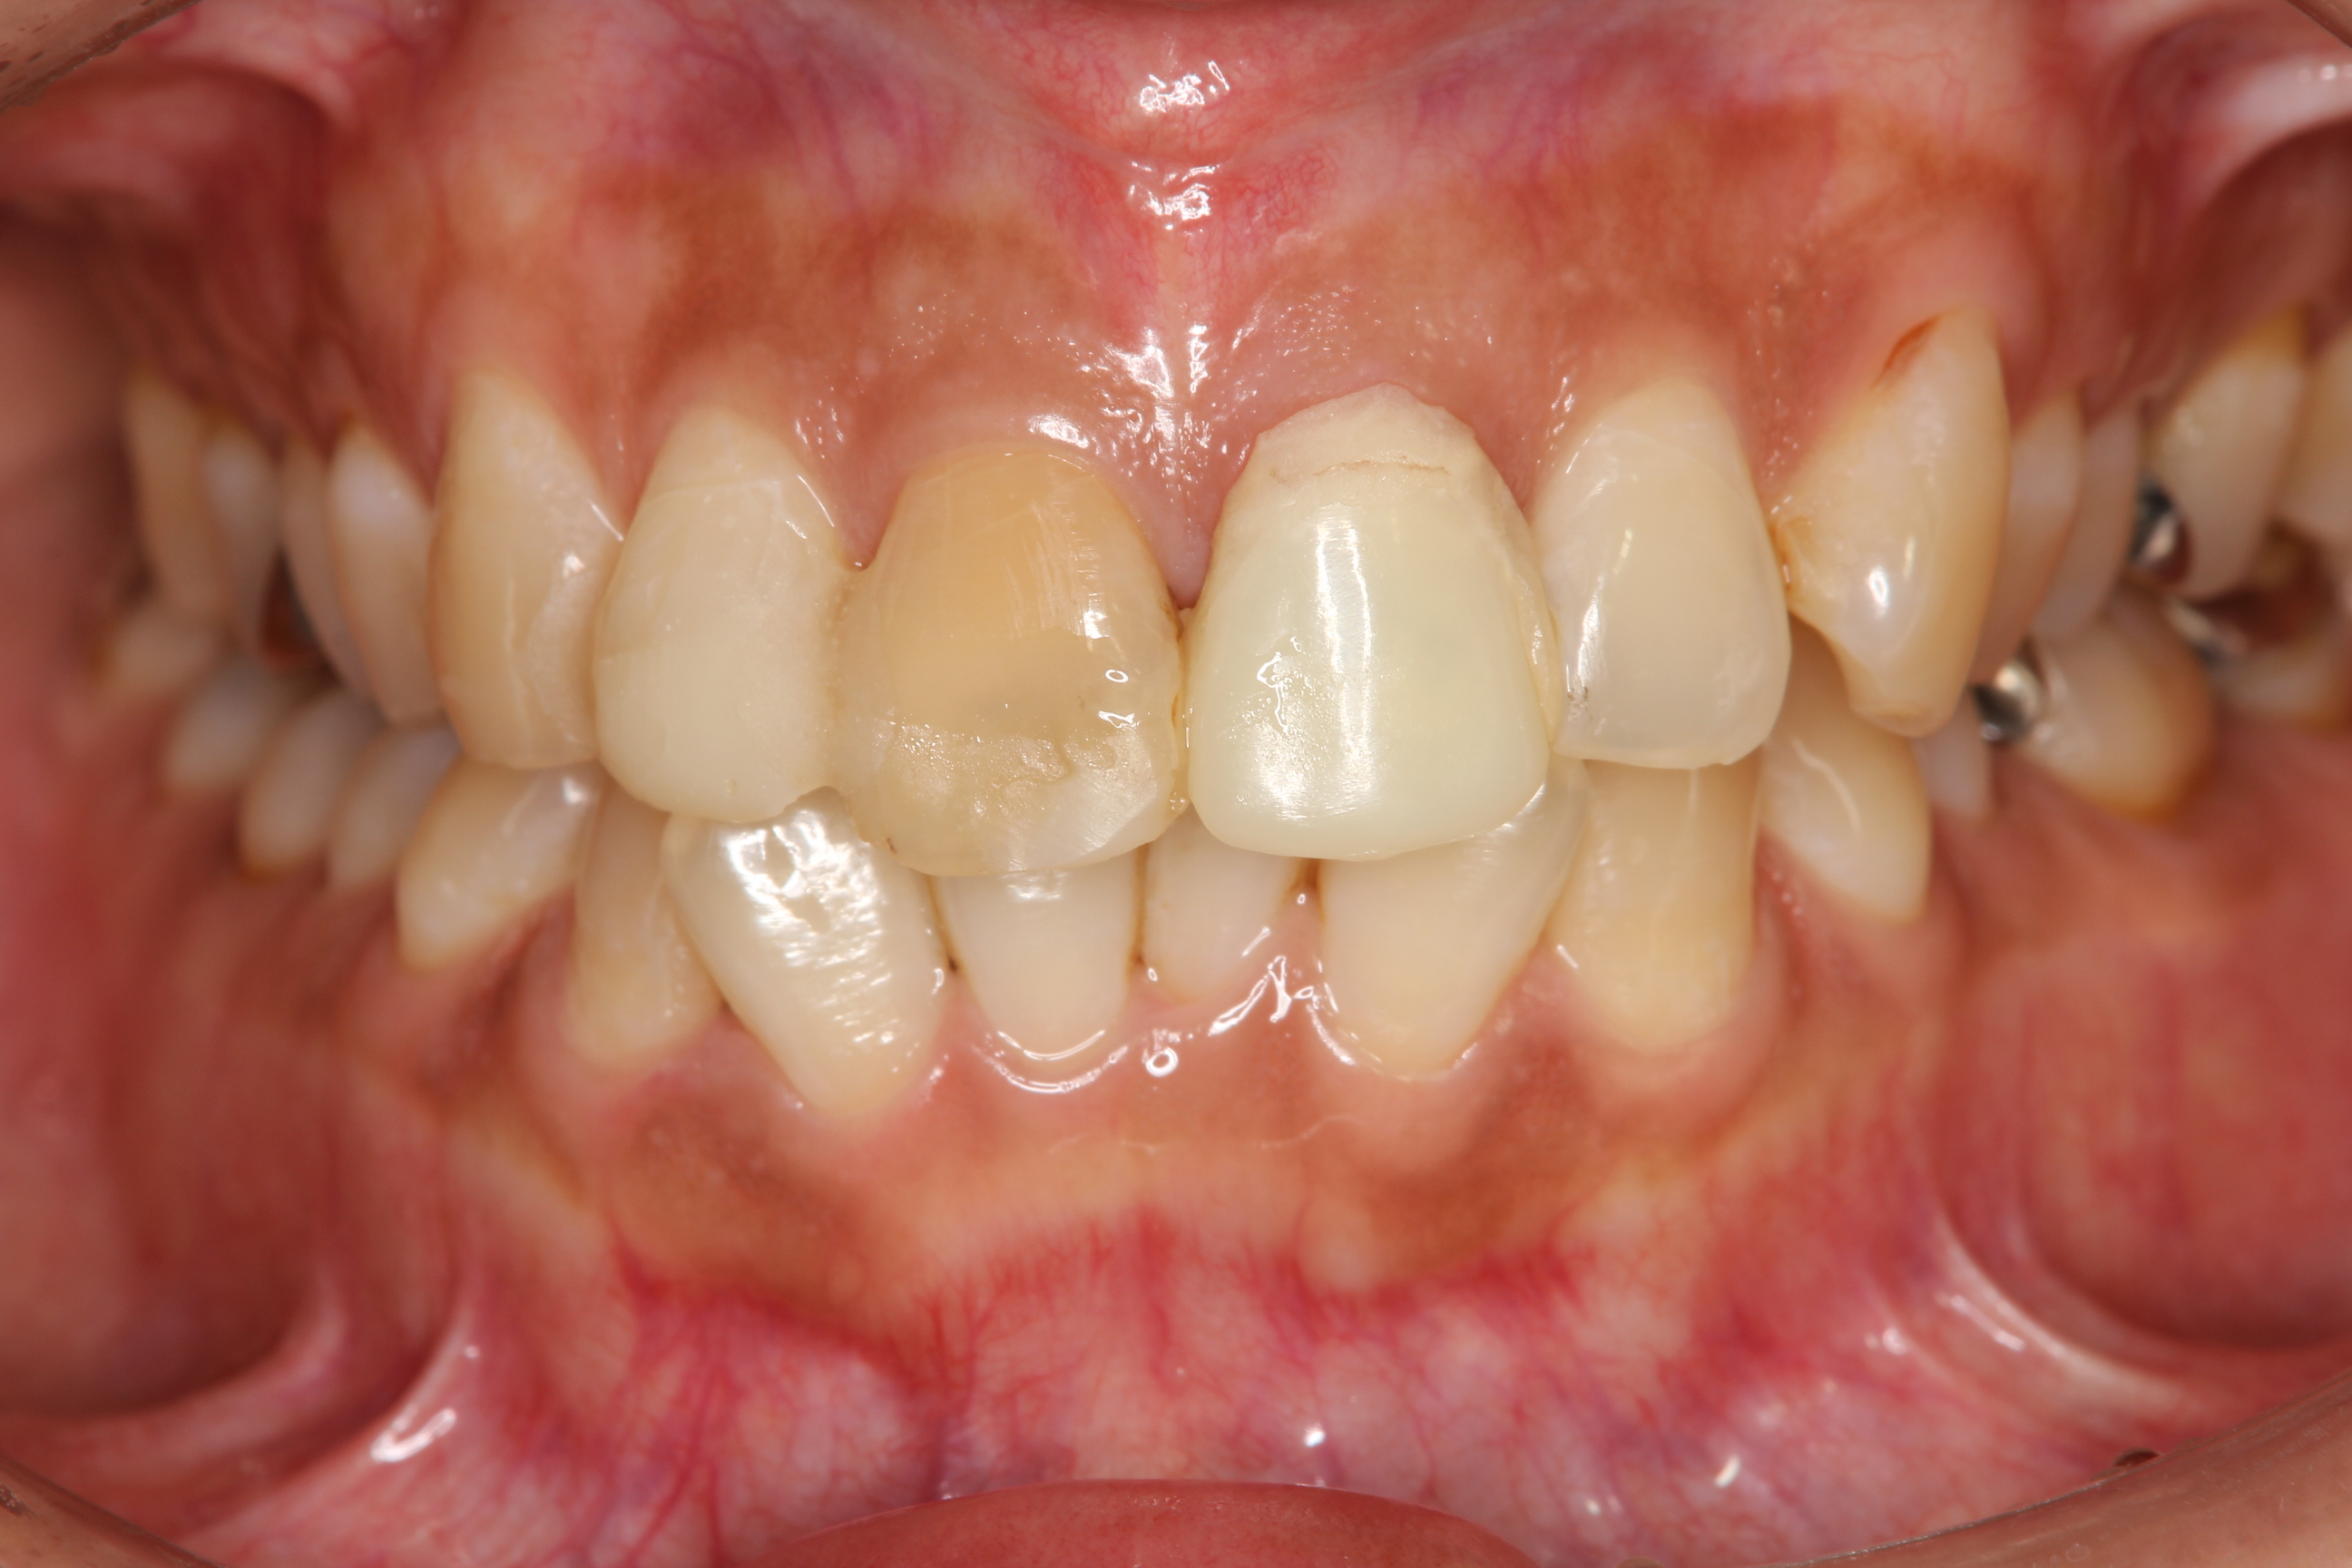

交通外傷で上顎前歯を殴打した患者さんです。

前歯の根管治療やMTM(部分矯正)、全顎的な歯周病治療を行い、クラウンを作製するための前処置が終了した状態です。

上顎4前歯の治療ですが、向かって一番右の歯はラミネートべニア。

その他の3前歯は、ジルコニアフレームのオールセラミックスクラウンによる治療を行います。

術後 術前

ジルコニアセラミックスクラウンとラミネートべニア装着

事故直後は腫れも痛みも強く前歯で全く噛めない状態でしたが、今ではそれも無くなり、

患者さんが気にされていた 歯の破折や色・形態も改善されました。